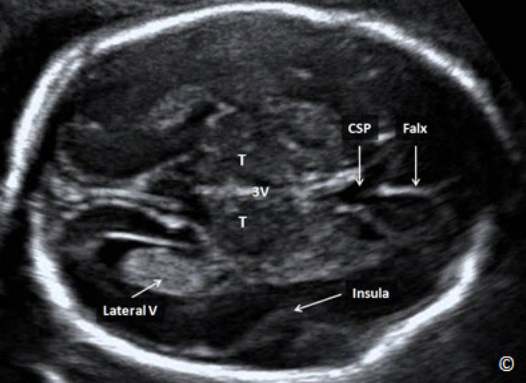

Biparietal Diameter

The Biparietal Diameter (BPD) (Figures 5.1 and 5.2) should be measured in a cross-sectional

view of the fetal head at the level of the thalami. Sonographic landmarks identifying the correct

BPD plane are listed in Table 5.3 and the procedure to measure the BPD is shown in Table 5.4.

On occasions, especially in the third trimester when the fetal head is engaged, the BPD can be

measured from a coronal plane of the head, if this is the only imaging option available.

Đường kính lưỡng đỉnh (ĐKLĐ) (Bảng 5.1 và 5.2) nên được đo theo mặt cắt ngang của

đầu ở ngang mặt cắt đồi thị. Các điểm mốc trên siêu âm của một mặt cắt lưỡng đỉnh

chuẩn được liệt kê theo Bảng 5.3 và cách thực hiện được liệt kê trong bảng 5.4. Trong

vài trường hợp, đặc biệt trong 3 tháng cuối, đầu xuống, ĐKLĐ được đo ở mặt phẳng

trán của đầu, nếu đây là lựa chọn duy nhất có thể

Figure 5.1: A transverse plane of the fetal head at the level of the biparietal diameter (BPD). In this

plane, you should see the cavum septae pellucidi (CSP), the falx (labeled), the thalami (T), 3rd

ventricle (3V) and the insula (labeled). A portion of the lateral ventricle is also seen (labeled).

Hình 5.1: Mặt cắt ngang của đầu ở đường kính lưỡng đỉnh. Ở mặt cắt này cho thấy vách trong suốt

(CSP), liềm não (Falx), đồi thị (T), não thất ba (3V), thùy đảo (insula) Một phần của não thất bên cũng

đươc ghi nhận ở mặt cắt này (Lateral V).

Sonographic Landmarks for the Measurement of the Biparietal

Diameter Plane (BPD). See Figure 5.1

- Midline Falx

- Thalami

- Symmetrical appearance of both cerebral hemispheres

- No cerebellum visualized

- Cavum Septae Pellucidi

- Insula

Mốc giải phẫu trên siêu âm ở mặt cắt đo đường kính

lưỡng đỉnh. Xem hình minh họa 5.1

- Liềm não ở đường giữa

- Đồi thị

- Sự hiện diện cân xứng cấu trúc 2 bán cầu não

- Không thấy tiểu não

- Vách trong suốt

- Thùy đảo

Plane at level of Biparietal Diameter

The sonographic landmarks identifying the correct BPD plane have been previously described in

this chapter (Figure 5.2) and include the midline falx, the cavum septae pellucidi and the

thalami. Abnormalities detected in this plane include ventriculomegaly (Figure 5.22 A and B),

holoprosencephaly (Figure 5.14), agenesis of the corpus callosum (Figure 5.23) and septo-optic

dysplasia (Figure 5.24). Other rare intracranial abnormalities, such as tumors, can also be

detected in this plane. Comprehensive evaluation of the fetal central nervous system requires multiple views of the fetal brain from its sagittal, coronal and axial (transverse) views and through the abdominal and transvaginal (when feasible) approach.